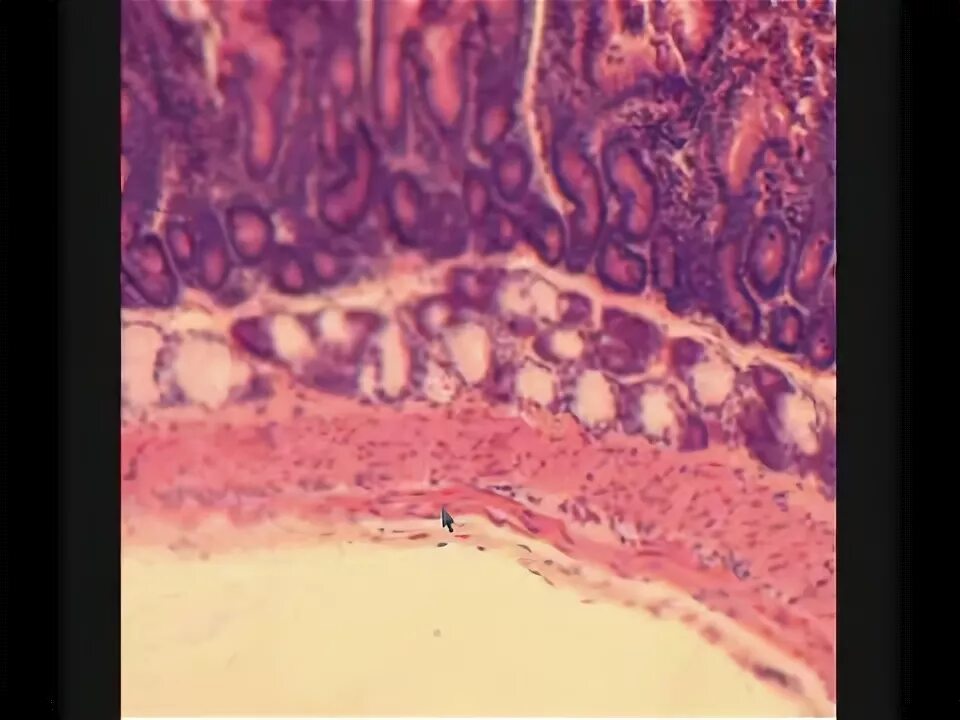

Электронная микроскопия тонкого кишечника